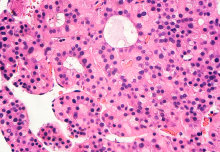

A previously overlooked cell membrane protein could help to further cancer research, drug design, and bioengineering, according to new research.

The protein, called syndecan-4, combines with fellow cell membrane proteins, called integrins, to form protruding ‘hands’ that sense the environment outside the cell.

Both proteins sit in the cell membrane, with one end pointing inside the cell and the other outside. They are therefore in a prime position to sense conditions outside the cell and convert signals to biochemical messages that change conditions inside the cell. In doing so, they’re able to drive some of the cellular processes behind cancer and other diseases.